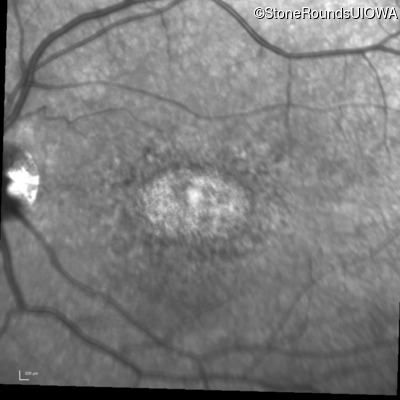

Infrared Fundus Photograph - Right - 20/100 +1

Exemplar

Infrared Fundus Photograph - Right - 20/80 -1

Infrared Fundus Photograph - Right - 20/100